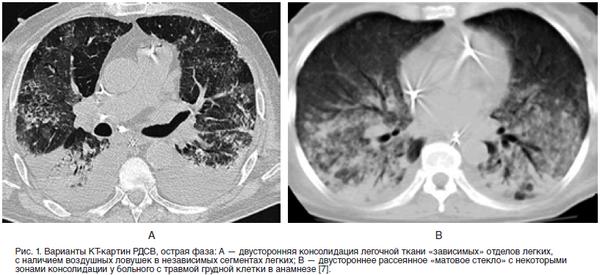

Консолидации кт

Консолидации кт 116 фотографий